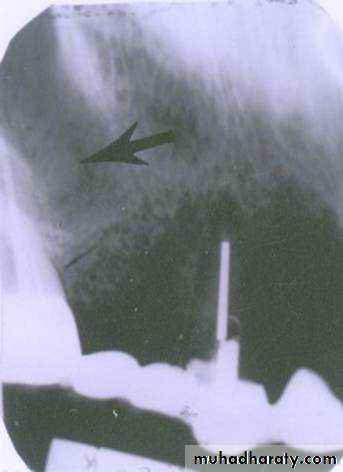

Is the maxillary second premolar (arrows) displaced to the buccal or the lingual?

premolar filmmolar film

premolar bitewing

4The tube head moves distally from the premolar film to the molar film. The second premolar also moves distally, overlapping the first molar more in the molar film. In moving from the premolar periapical to the bitewing, the tube head moves down and the premolar also moves down. The displacement is to the lingual.